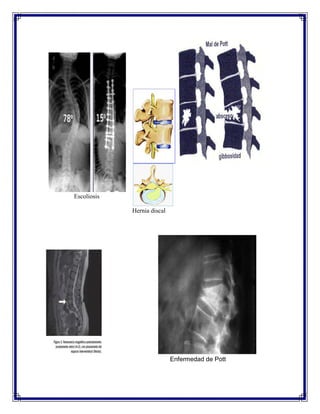

1. ESCOLIOSIS

Se define como la desviación y rotación laterales de una serie de vértebras a partir de la

posición anatómica central en la línea media, que representa el eje de la columna. La

deformidad se produce en tres planos: frontal, sagital y transverso.

2.-FISURA, PROTRUSIÓN O HERNIA DISCAL

La fisura discal consiste en el desgarro de la envoltura fibrosa del disco. La forma màs

tìpica es la fisura radial, en la que el desgarro es perpendicular a la dirección de las fibras.

La protrusión discal consiste en la deformación de la envuelta fibrosa por el impacto del

material gelatinoso del núcleo pulposo contra ella. Si la envuelta llega a romperse y parte

del núcleo pulposo sale fuera de la envuelta, se diagnostica hernia discal.

6.-ENFERMEDAD DE POTT

La tuberculosis es una infección bacteriana crónica causada por Mycobacterium

tuberculosis. La tuberculosis vertebral es la localización más frecuente después de la

tuberculosis pulmonar. Entre un 25 y un 50 por ciento de los casos de tuberculosis

esquelética van a afectar a la columna vertebral. Es la denominada espondilitis tuberculosa

o enfermedad de Pott.

La lesión inicial afecta al ángulo anterosuperior o inferior del cuerpo vertebral.

Radiológicamente, suele observarse la afectación de dos cuerpos vertebrales vecinos, con

acuñamiento anterior y con destrucción del disco intervertebral. Esto provoca una cifosis,

generalmente sin escoliosis. Aproximadamente, la mitad de los enfermos presenta algún

grado de debilidad o parálisis en las extremidades inferiores. Afecta, principalmente, a la

columna dorsal inferior, siguiendo en frecuencia la zona lumbar

Escoliosis

Hernia discal

Enfermedad de Pott